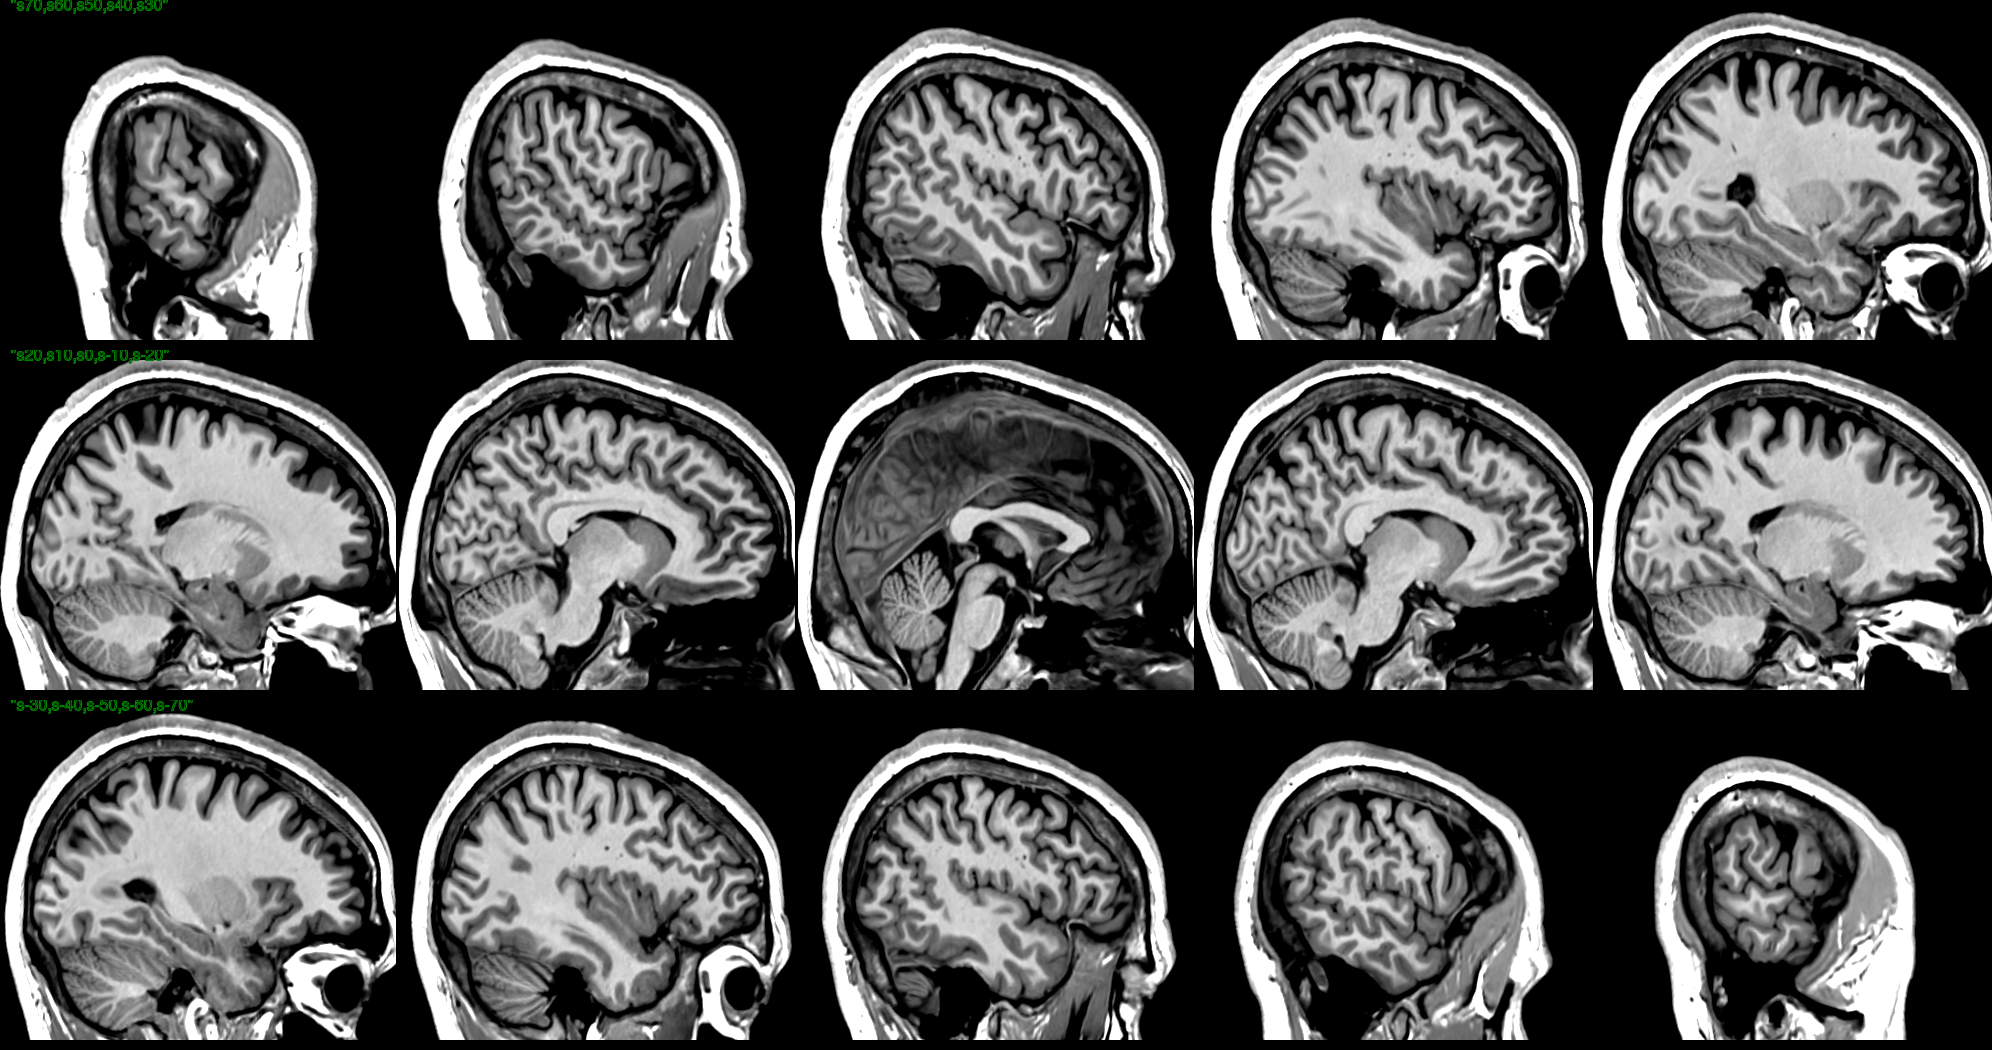

T1 Images